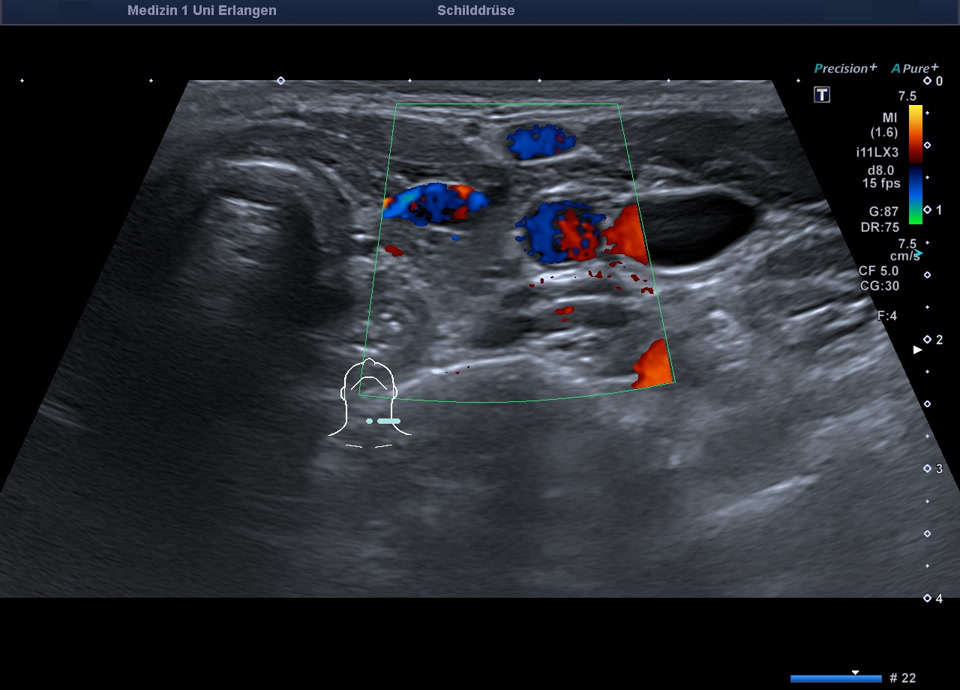

36-year-old patient with tremor, tachycardia, exophthalmos, and weight loss. Thyroid ultrasound shows bilaterally hypoechoic, inhomogeneous parenchyma with a total volume of 20.5 ml. Color Doppler sonography shows hypervascularization. Laboratory results: basal TSH decreased, T3/fT4 elevated, TRAK positive, consistent with Graves’ disease. Symptoms resolved under treatment with thiamazole and propranolol. At follow-up two years later, sonography showed a hyperechoic minimally inhomogeneous parenchyma with normal volume (15 ml).